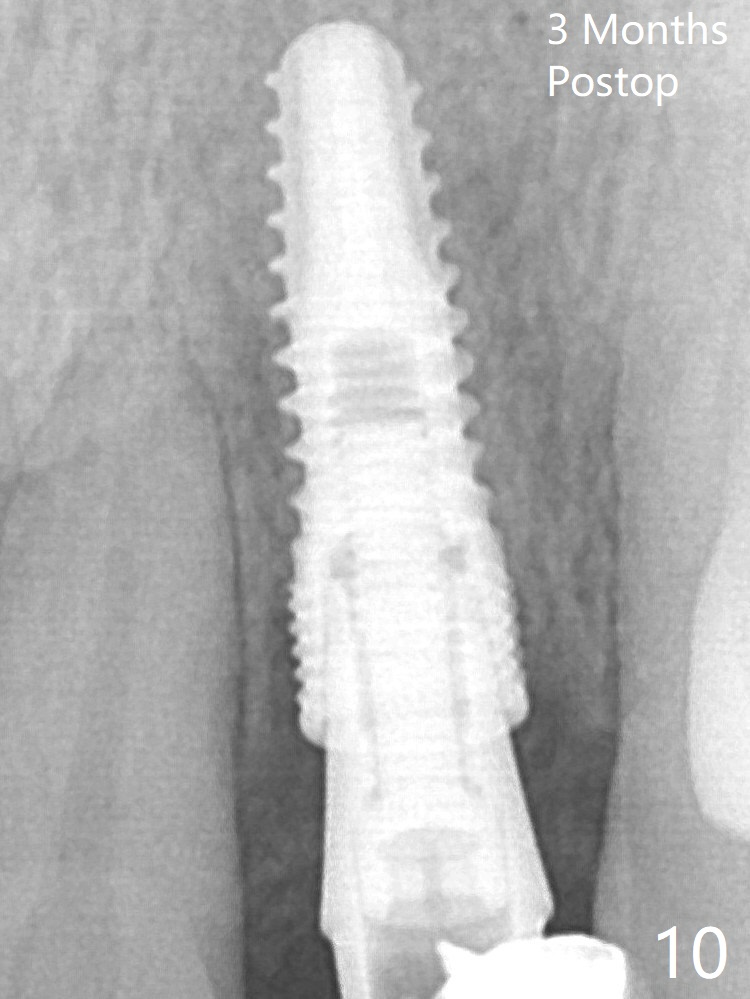

After a 3.8x12 mm SM implant is placed (Fig.4), allograft is packed in the periimplant space (*).  The patient returns for impression 3.5 months postop (Fig.10).